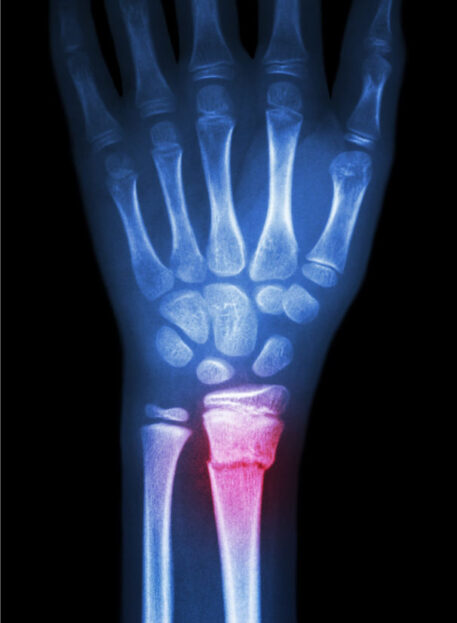

01. Možni zapleti – zlom čolnička (os scaphoid)

Pri poškodbah zapestja je vedno treba izključiti zlome, zlasti zlom čolnička (os scaphoideum).

Značilni znaki:

- bolečina v anatomski tobačnici (tabatiere anatomique)

- bolečina ob palmarni in dorzalni fleksiji

- bolečina ob radialnem odmiku in pritisku na čolniček

02. Diagnostika

Za natančno diagnozo uporabljamo:

- klinični pregled z otipom in testi gibljivosti

- slikovne preiskave (RTG, MR) ob sumu na zlom

Pravilna diagnostika je ključna, da ne spregledamo resnejših poškodb.